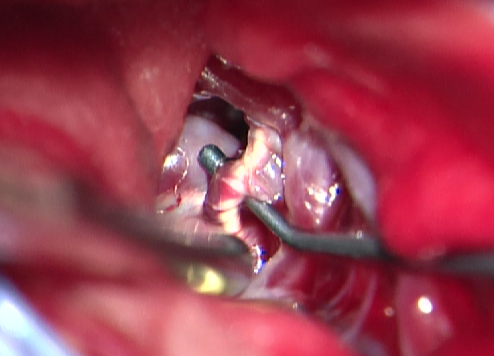

3.开颅手术切除畸形血管团

考虑到患者术前癫痫,且介入术中患者拔管困难,予以行开颅手术切除畸形血管团,并拔出微导管。术中可见微导管及注射的Onyx胶(血管内黄色部分及黑色部分),游离血管后近端用临时阻断夹阻断,远端剪断,打开临时阻断夹将微导管自股动脉鞘拔出,然后切除畸形团。术后复查头颅CT提示钙化及介入术中胶均已切除。